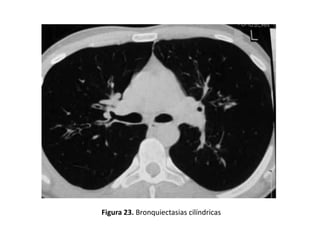

• Cilíndricas:

– Son las más frecuentes.

– Los bronquios están mínimamente dilatados de

manera uniforme, no adelgazan su diámetro al

progresar las generaciones y pueden verse sus

paredes como líneas paralelas en cortes

longitudinales (Figuras 10, 13 y 23).

Figura 23. Bronquiectasias cilíndricas